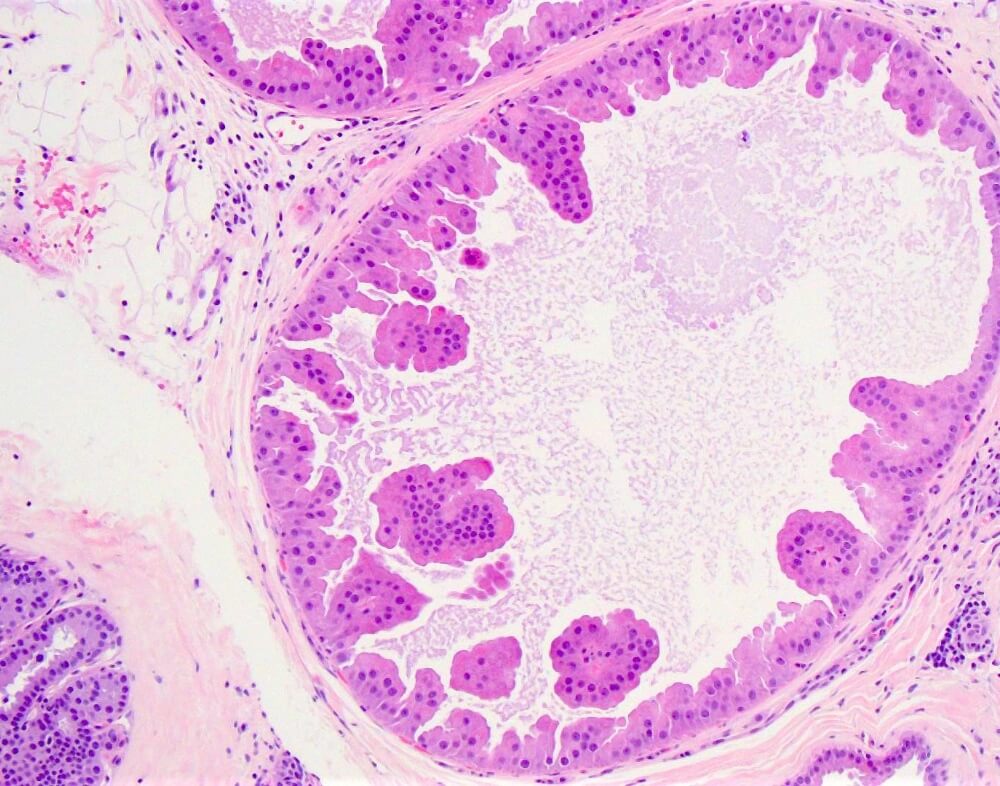

Συχνά ανευρίσκεται στο τοίχωμα κύστεων ή διατεταμένων γαλακτοφόρων πόρων ή μέσα σε άλλες αλλοιώσεις όπως η αδένωση και τα ενδοπορικά θηλώματα.